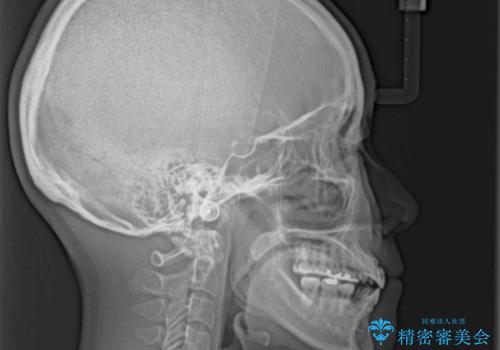

- 学生時代に行った抜歯矯正の後戻りで、隙間ができてしまったことを気にして来院された患者様です。

マウスピース矯正を検討されていましたが、後戻りの隙間が非常に大きく、奥歯を前方に移動させる必要があるため、ワイヤー装置にて矯正治療を行うこととしました。